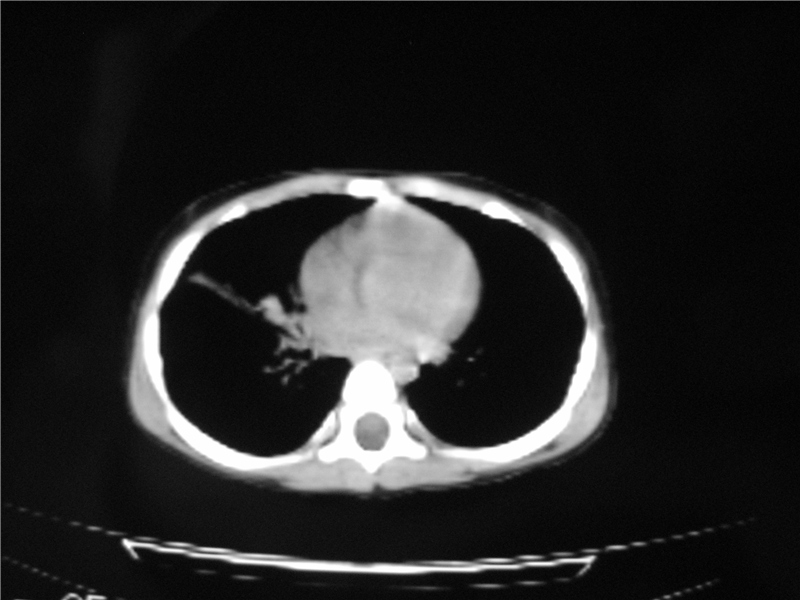

标题: PED3236:男2岁进食花生米后发烧10天。

右肺中叶及下叶内段大片实变密度增高影,可见支气管气象,肺炎.

摄吸气及呼气相对比片,本例为有肺中叶阻塞性炎症、不张,右肺下叶阻塞性炎症。

1)右肺炎症并右肺中叶肺不张,右肺上叶充气不良。2)右侧支气管异物不排除。

结合临床考虑支气管异物并阻塞性肺炎、肺不张。

右肺中叶及下叶内段大片实变密度增高影,可见支气管气象,肺炎.  ------异物阻塞所致!建议去除!